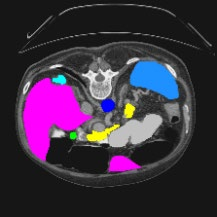

Transformers have made remarkable progress towards modeling long-range dependencies within the medical image analysis domain. However, current transformer-based models suffer from several disadvantages: (1) existing methods fail to capture the important features of the images due to the naive tokenization scheme; (2) the models suffer from information loss because they only consider single-scale feature representations; and (3) the segmentation label maps generated by the models are not accurate enough without considering rich semantic contexts and anatomical textures. In this work, we present CASTformer, a novel type of generative adversarial transformers, for 2D medical image segmentation. First, we take advantage of the pyramid structure to construct multi-scale representations and handle multi-scale variations. We then design a novel class-aware transformer module to better learn the discriminative regions of objects with semantic structures. Lastly, we utilize an adversarial training strategy that boosts segmentation accuracy and correspondingly allows a transformer-based discriminator to capture high-level semantically correlated contents and low-level anatomical features. Our experiments demonstrate that CASTformer dramatically outperforms previous state-of-the-art transformer-based approaches on three benchmarks, obtaining 2.54%-5.88% absolute improvements in Dice over previous models. Further qualitative experiments provide a more detailed picture of the model's inner workings, shed light on the challenges in improved transparency, and demonstrate that transfer learning can greatly improve performance and reduce the size of medical image datasets in training, making CASTformer a strong starting point for downstream medical image analysis tasks.